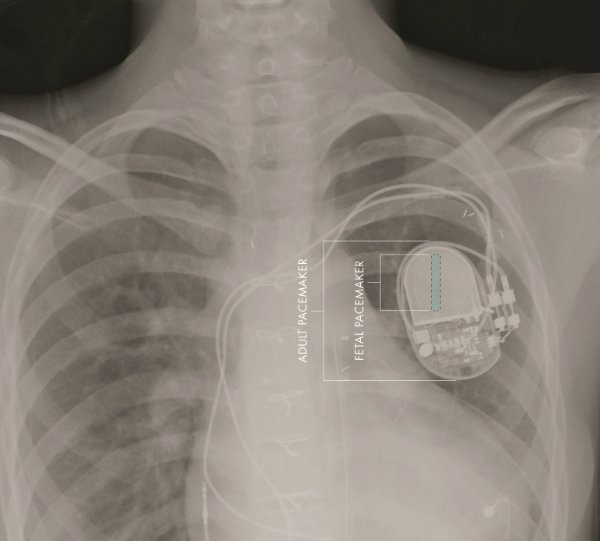

В отличие от таких экспериментов новое устройство является достаточно небольшим, чтобы быть имплантированным непосредственно в ребенка. Независимо от того, как двигается малыш, компоненты кардиостимулятора остаются все в одном месте. На снимке можно увидеть относительные размеры стандартного кардиостимулятора и новой модели устройства для плода.